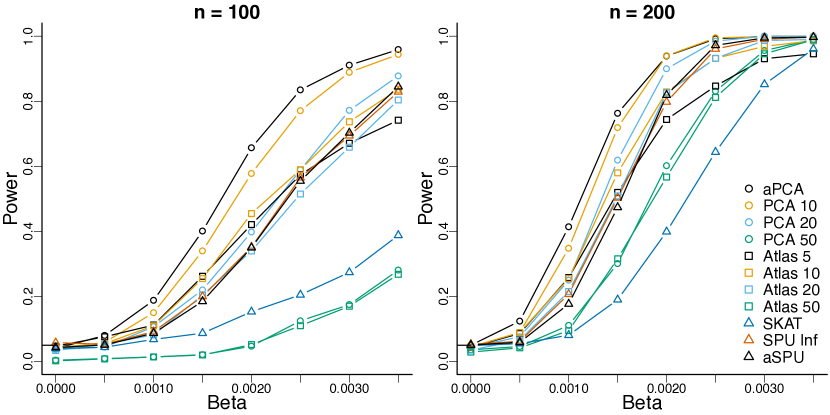

We perform 1000 simulations for sample sizes of and compare the PST for the adaptive procedure and fixed bases with dimensions of . In addition, we compare the PST to the sequence kernel association test (SKAT) (Wu et al., 2011), the sum of powered scores (SPU) test using the infinity norm, and the adaptive sum of powered scores test (aSPU) (Pan et al., 2014). We assess pointwise power and type 1 error of the PST inference with uncorrected, Bonferroni-corrected, and BH-corrected results. We also compare FWER and FDR between methods. For these comparisons we assess the type 1 error for the unprojected scores using inference designed for the projected scores.

The PST with fixed bases demonstrates superior power to the other tests (Figure 3), due to its ability to remove the influence of unassociated scores from the test by maximizing over the basis and by leveraging the spatial information in the data. If these features of the data were not informative then the PST would not perform well. The aPCA is has better power than the other PCA bases because a low rank basis is all that is required to capture the signal in the data. aSPU is adaptive to the sparsity of the signal, so it performs better than the SKAT, but does not use the information in the covariance of the scores to leverage power.